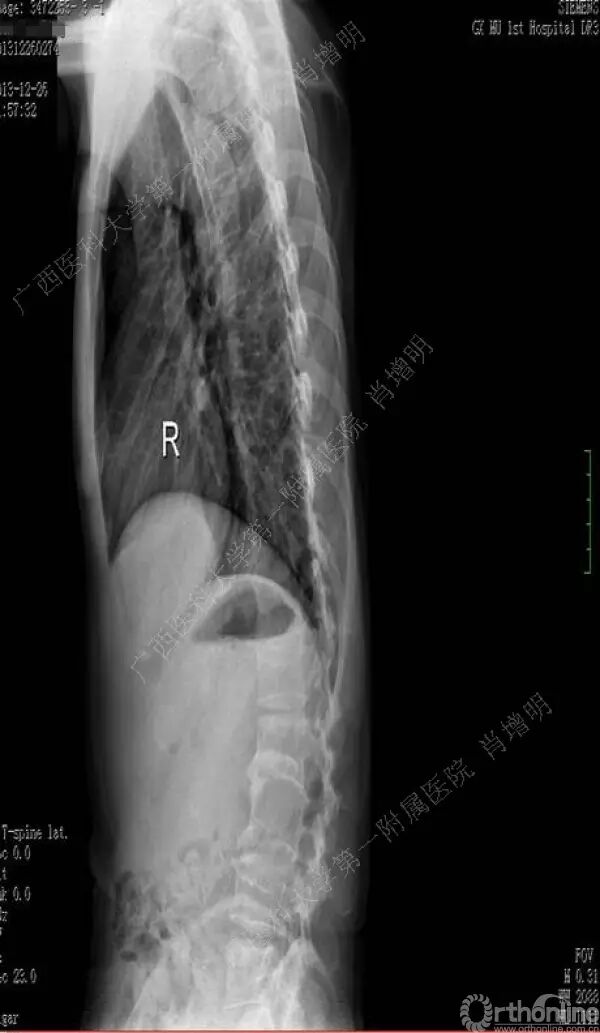

退变性脊柱侧凸是由于椎间盘退变后继发小关节退变,椎管和神经根管容积变化以及脊柱失稳,畸形等病理改变,以疼痛和神经压迫症状为主要表现的常见疾病。

退变性脊柱侧凸多发于50岁以上的中老年群体,是现代常见的老年疾病。多年来,针对该病的临床研究一直没有停步,广西医科大学第一附属医院肖增明教授细致地介绍了该病的诊疗进展。